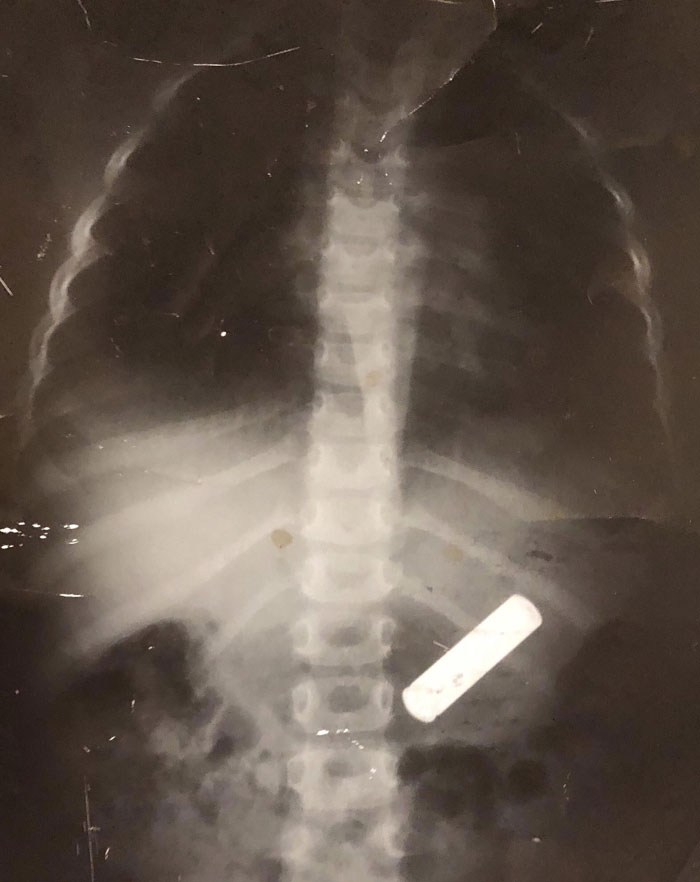

Someone Took "The Key To The Heart Is Through The Stomach" A Bit Too Literally